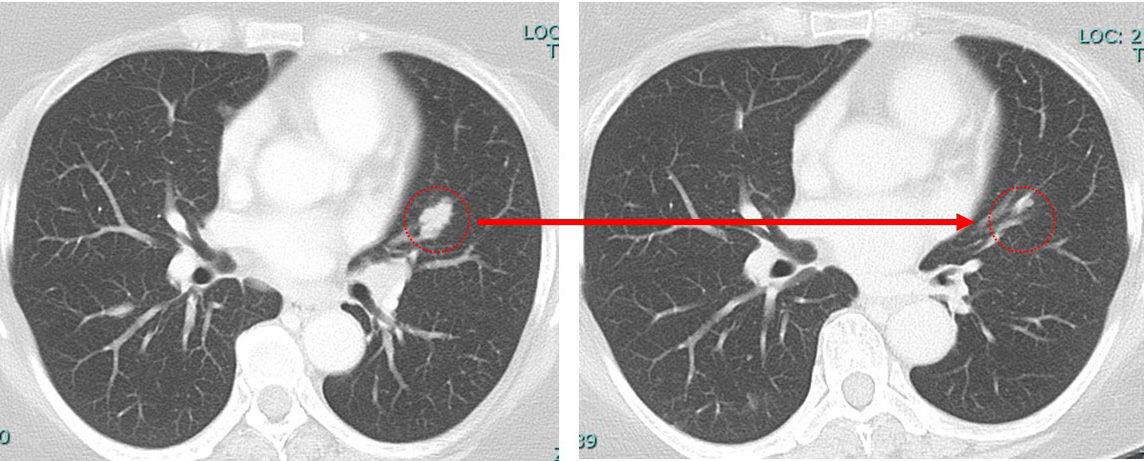

①「多発肺転移」は画像上かなり小さくなっているのに「胸の腫瘍は小さくならない」

この「乖離」が何故なのか?

②2年半もの治療期間で「小さくならなかった(効果がなかったといえる)」この原発巣が(このままの治療で)いずれかの時点で「新たな遠隔転移の原因とならないのか?」

原発巣は大きい(腫瘍細胞の量が膨大)に対して肺に(多発してはいるが)「それぞれの腫瘍の細胞量は少ない」

その意味で私のよくいう「volume reduction」というのは理に適っている。

このvolume reductionの考えの延長線上に「局所療法の重要性がある」とも言えます。

少数臓器のオリゴ転移(oligometastatic disease:OMD)に対しては転移巣を切除することで臨床成績の改善が得られる可能性が論じられるようになってきた。

転院、そして手術 Bt+Ax+Ic, (レベルⅢまで郭清しましたが、幸いリンパ節転移はレベルⅠに1個のみでした。乳腺腫瘍は33mm)

anthracyclin終了時の時点でのCTでcCR